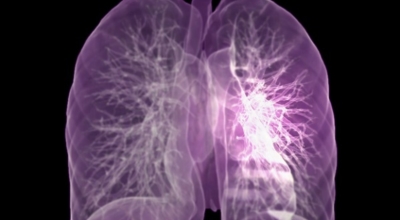

폐에 발생된 악성 종양을 말하며 오랜 기간 흡연해온 남성들에서 발병률이 높고 요즘 들어 가지가지 환경적인 요인의 영향과 간접흡연으로 흡연하지 않는 여성에서도 많이 발생하고 있답니다. 증상을 느껴 병원을 찾았을 때는 수술하기 늦은 경우가 많아 사망 확률이 매우 높은 암입니다. 폐 자체에서 생기거나 다른 장기에서 발생된 암이 폐로 전이되어 나타나기도 하고 특별한 초기 증상이 없는 경우가 많으며 암이 진행된 후에도 일반적인 감기 증상인 기침과 가래 외의 특이 증상이 나타나지않아 증상만으로는 진단이 쉽지 않아요.

폐암 검사는 X-ray를 통해서 검사하는데 , 크기가 작거나 구석에 위치한 경우 확인이 어려운 경우도 있습니다. 그리고 조직 검사를 통해서 정확한 진단을 하게 돼요. 폐암이 발견되면 종양의 크기나 전이 여부 , 위치에 따라서 수술 여부를 결정하게 돼요.